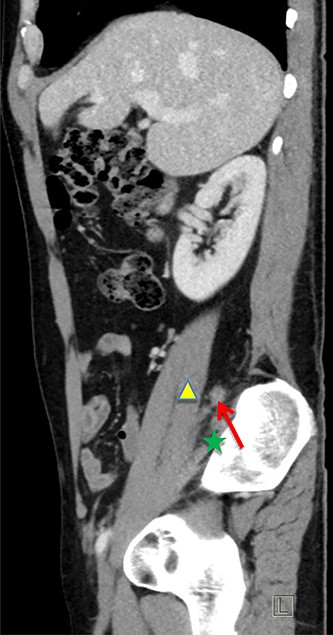

The patient was re-admitted and examination revealed a soft abdomen with localized rebound tenderness in the right iliac fossa. A computed tomography (CT) abdomen was requested and a referral made to the surgical team. The CT scan illustrated AA with the appendix located posterior to the ileo-psoas muscle (Figs 1–3). A diagnostic laparoscopy was performed, which revealed the head of the inflamed appendix herniated posterior to the psoas muscle in a cavity, (~25 mm deep and 10 mm in diameter) that could not be dissected laparoscopically (Fig. 2). Therefore, an uncomplicated open appendectomy was performed and the patient was admitted for post-operative observation. Recovery was uneventful and the patient was discharged without follow-up.

Coronal CT image. Inflamed appendix (red arrow) positioned between psoas (yellow triangle) and iliacus muscles (green star).